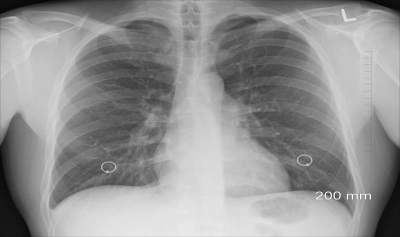

Apoi, femeia - profesoară într-un liceu din SUA - a fost testată pentru tuberculoză, iar rezultatul a fost negativ pentru această boală. Cu toate acestea, când i s-a făcut o radiografie, a fost descoperită o leziune în lobul superior drept al unuia dintre plămâni. În urma investigațiilor suplimentare, aceasta părea a fi "o structură inversată asemănătoare unui sac 'așezat' în bronhii".